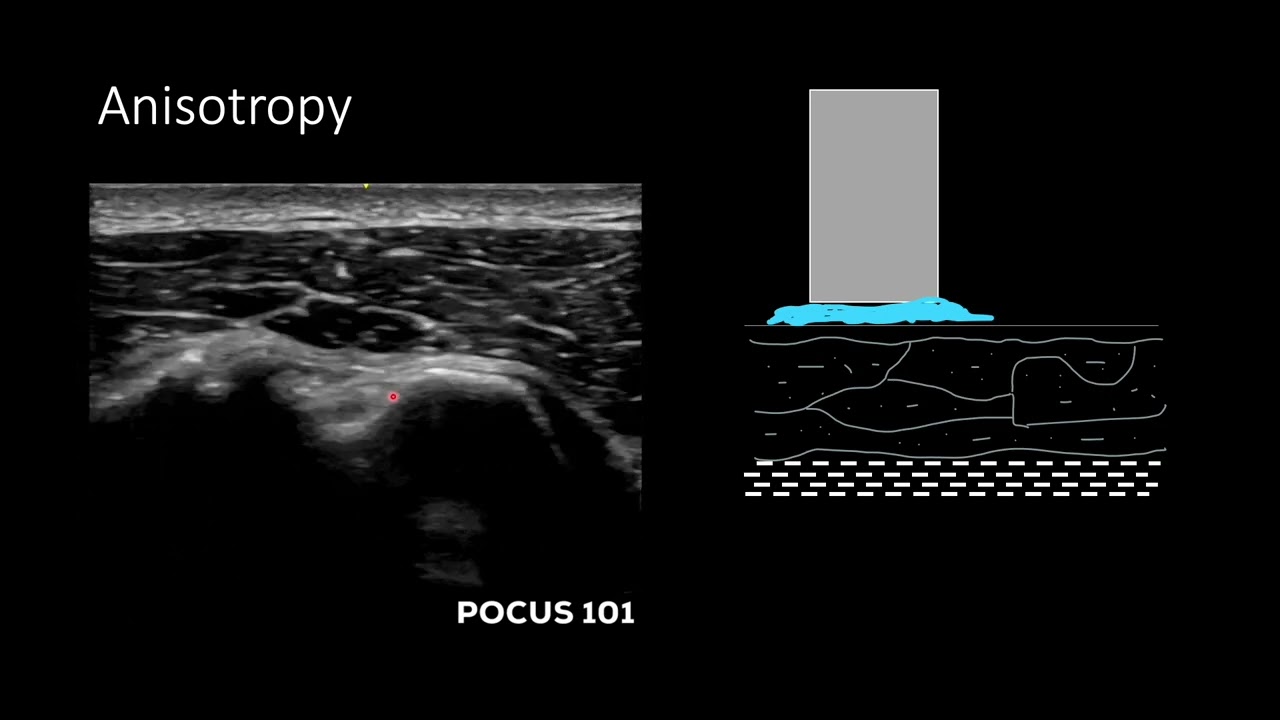

🔍 How to recognize key ultrasound artifacts (like shadowing, anisotropy, and reverberation)